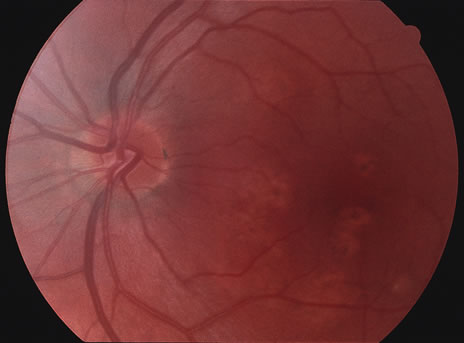

Some patients present with subretinal bands that extend between chorioretinal scars. In addition there may be initial active yellow choroidal lesions that subsequently become atrophic. Vitreous cells are usually present although they may be few and difficult to detect. Visual acuity loss in these cases may be due to active choroidal neovascularization, subretinal bands under the fovea, or from cystoid macular edema. The vast majority of affected patients are women with a mean age of 27 years and both eyes are usually involved. The affected individuals tend to be myopic.49 The age range is from 6 years to 76 years and there is no racial predilection.40 Whether it is a separate disease or a more severe form of multifocal choroiditis is controversial (Figs. 10 and 11). Aggressive therapy is warranted because it has a poorer prognosis than most cases of multifocal choroiditis. This syndrome has been called either diffuse subretinal fibrosis or progressive subretinal fibrosis syndrome.

Fig. 11. A. Subretinal fibrosis in a case of multifocal choroiditis. B. Fellow eye showing classic coalescent hyperpigmented chorioretinal scars of multifocal choroiditis. These scars also can be seen in presumed histoplasmosis syndrome, but the subretinal fibrosis is extremely rare in presumed ocular histoplasmosis syndrome (POHS).